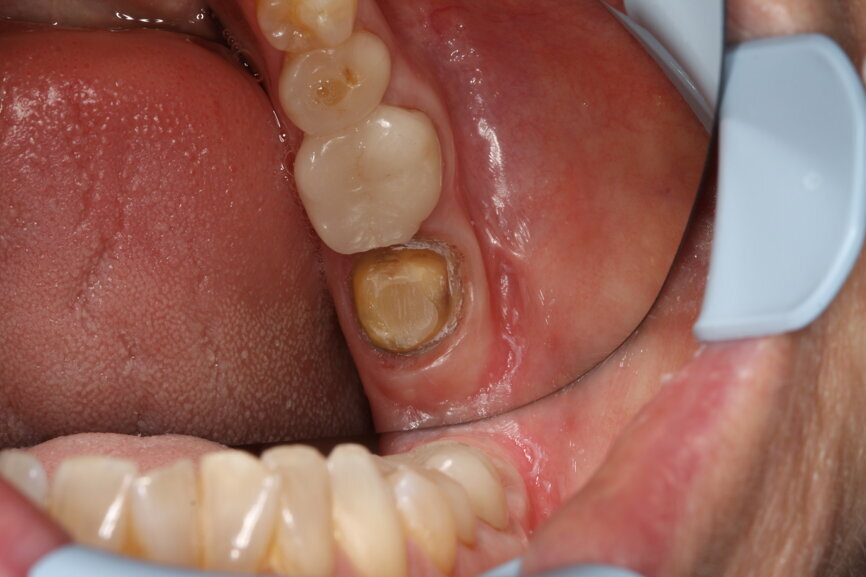

Initial situation of tooth #37. (Image: Dr Bernhild-Elke Stamnitz, Germany)

A case history demonstrates how CEREC Primescan proves its worth in everyday practice. A patient came to the practice with an inadequate crown, with secondary caries, in position #37. After excavation, a new CEREC crown was to be mounted. In order to do so, the new acquisition centre, CEREC Primescan AC, with its significantly larger, tiltable touch screen, was first disinfected. Thanks to the seamless surfaces, it is possible to do so quickly, thoroughly and simply, at any time. Before beginning with the scans, the patient data was retrieved in CEREC Primescan AC, and a new case was created. Overall, the scanner was used three times during treatment: after preparation of the lower dental arch with tooth #37, for the scan of the opposing dental arch and for the scan of the buccal bite on both sides.